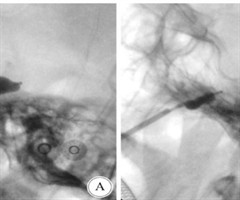

改良经皮穿刺球囊压迫术与微血管减压术治疗单纯第Ⅲ支三叉神经痛的对比研究

【摘要】目的探讨改良经皮穿刺球囊压迫术(PBC)与微血管减压术(MVD)治疗单纯第II支三叉神经痛的疗效差异。方法纳入西湖大学附属杭州市第一人民医院2019年1月—2021年12月收治的186例单纯第IⅡ支原发性三叉神经痛患者,其中57例采...